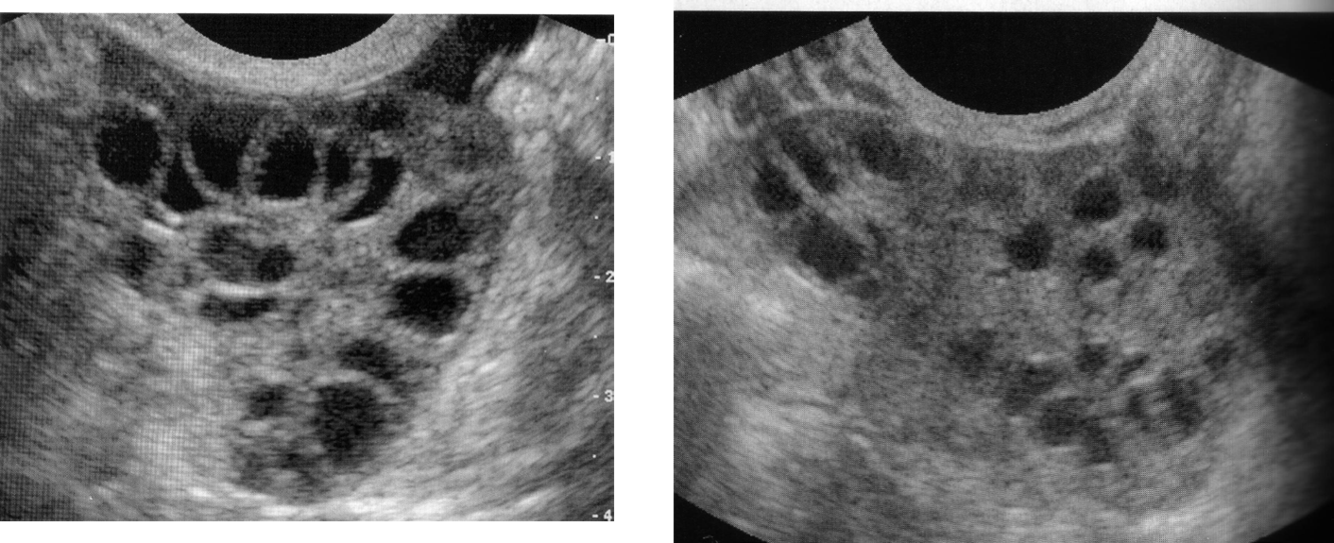

Ovarian Stimulation

Oocyte retrieval

Ovarian Hyperstimulation Syndrome